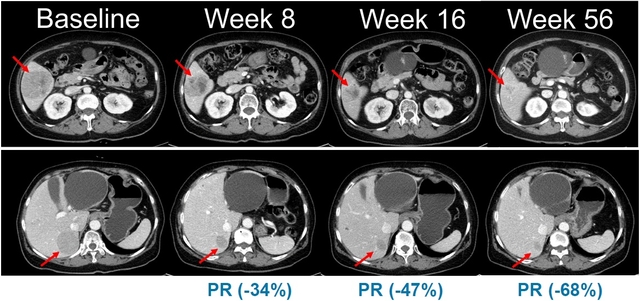

벨바라페닙과 코비메티닙 병용요법 임상시험에서 시간 경과에 따른 병변 변화가 관찰된 복부 CT 영상. 한미약품 제공